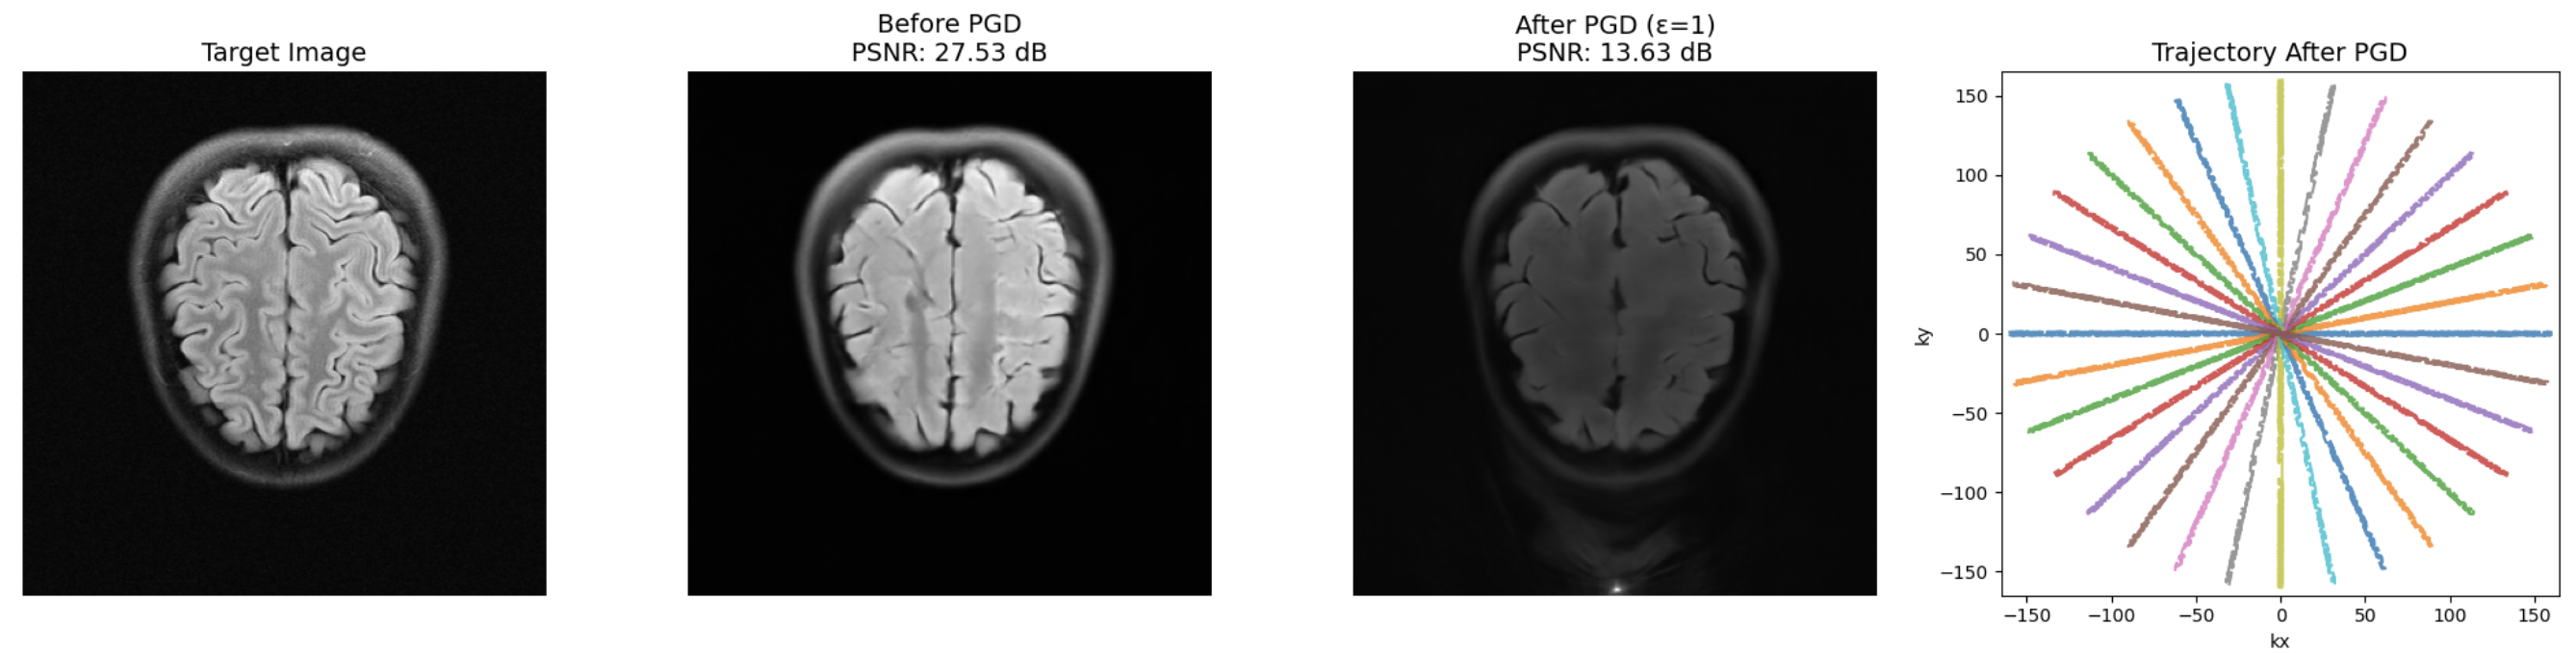

Refer to caption

Figure 3: Standard traj. noise (PT-ViT-L).

Figure 4: Adversarial traj. noise (PT-ViT-L).

Noise parameters for all DG methods were tuned to balance two goals. The noise must be strong enough to cause noticeable degradation when applied to clean-trained models, confirming a meaningful distribution shift, yet moderate enough to preserve strong in-domain performance on fastMRI. Specifically, we used τ=10\tau{=}10 (Cartesian) and τ=30\tau{=}30 (Radial) for Trajectory Noise, ϵ=1\epsilon{=}1 and numBits=4numBits{=}4 for Adversarial Trajectory Noise, and σ=6×105\sigma{=}6{\times}10^{-5} for Image Noise. This calibration ensures realistic robustness evaluation while maintaining fair cross-method comparison.